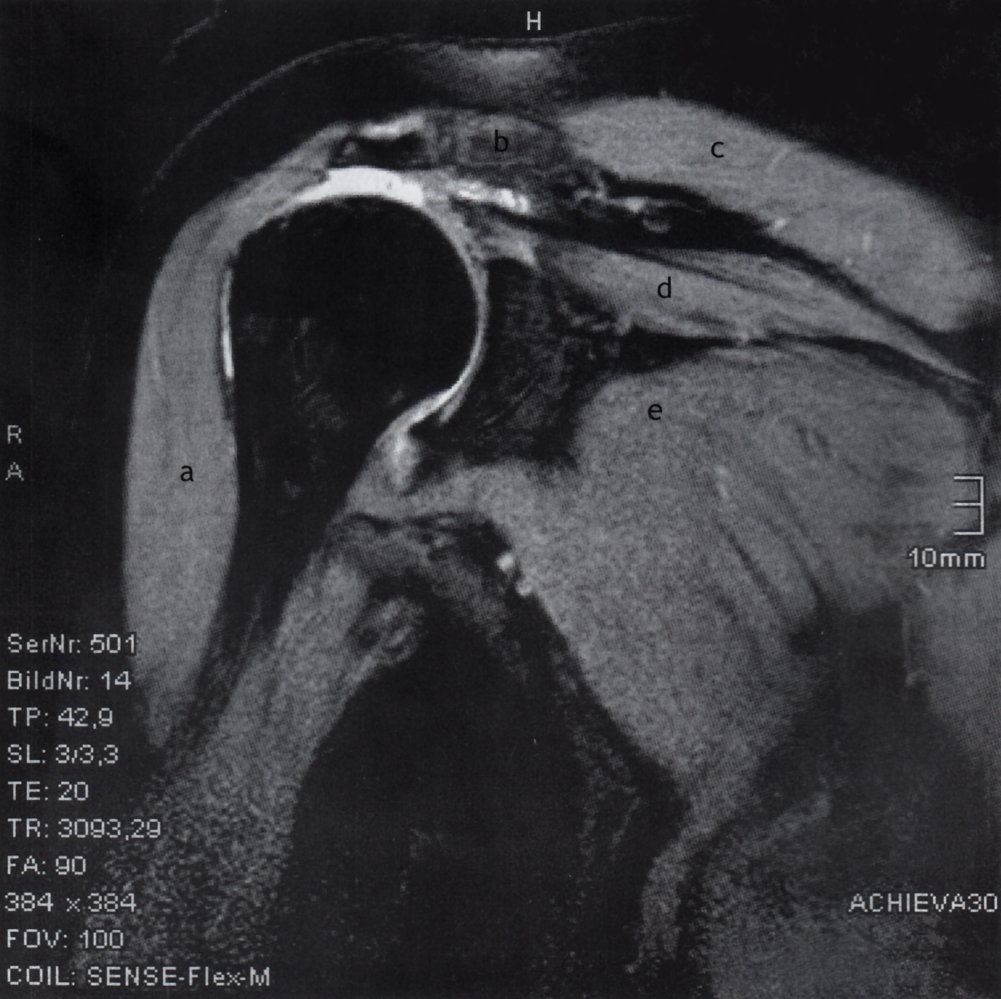

• Imaging

• X-ray shoulder: may show signs of rotator cuff damage

• MRI shoulder: may show large joint effusion, significant rotator cuff tears, synovial hypertrophy, and calcification and destruction of cartilage at the articular surface

Milwaukee shoulder syndrome is associated with an extensive loss of articular cartilage, destruction of the humeral head, rotator cuff defects, large effusion, and small osteophytes. Conversely, OA is typically associated with prominent osteophytes, an intact rotator cuff, and humeral head sclerosis. [9]